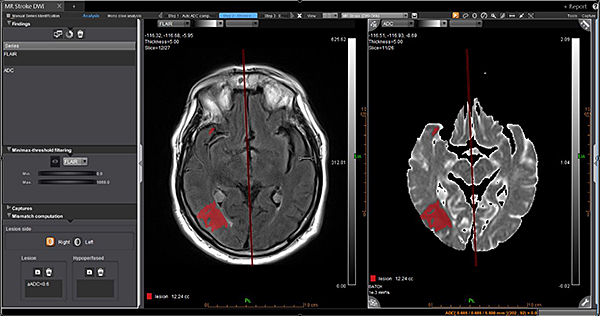

Дослідження інсульту MR Acute Care Stroke.

Незалежно від важкості невідкладного стану, ці додатки надають радіологам прямий доступ до звіту про інсульт в найкоротші терміни. Ці додатки включають інформацію про кровотік за допомогою унікальних динамічних порогових карт перфузії для візуальної оцінки гіпоперфузованих ділянок та використання методу Байєса для зменшення дози контрасту наполовину для перфузійного дослідження мозку.

Додаток Basic Stroke

Додаток Basic Stroke інтегровано у розширену візуалізацію Vitrea. Він надає радіологам прямий доступ до звітів про інсульт на будь-якому етапі невідкладного стану.

Забезпечує доступ до повного набору інструментів постпроцессингу і аналізу параметрів, карт та показників в будь-якому місці і в будь-який час.

Повністю автоматизований робочий процес економить час пацієнтам, які перенесли інсульт.